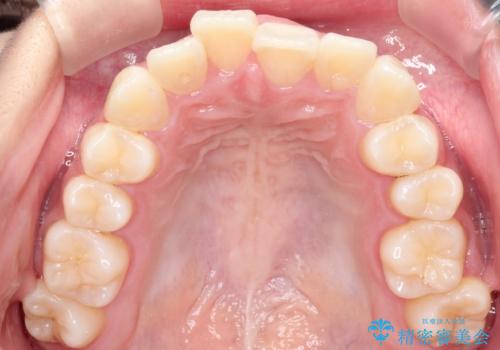

前歯の叢生・Ⅱ級咬合を改善|TADを用いた遠心移動+インビザライン矯正

- 前歯のガタガタと臼歯関係のⅡ級(上顎の歯列が前方にある状態)を改善するため、TAD(歯科矯正用アンカースクリュー)を使用したインビザライン矯正を計画しました。まずTADを上顎の適切な位置に設置し、それを固定源にして奥歯を後方(遠心)へ移動させ、十分なスペースを確保します。その後、インビザラインによるマウスピース矯正で前歯の歯列を整え、臼歯関係を正常化します。治療期間はおよそ1年半〜2年を想定しています。

前歯部の叢生(ガタガタ)と臼歯関係のズレを改善するため、抜歯をせずに奥歯を後方へ移動(遠心移動)させることを選択しました。TADという小型のアンカースクリューを顎骨に設置することで、確実かつ効率的に奥歯を後方へ移動させました。併せて透明で目立ちにくいインビザラインを用いることで、審美性を保ちながら治療を進めることが可能でした。患者様の負担が少ないマウスピース矯正と固定源のTADを組み合わせることで、抜歯することなく歯並びと噛み合わせを大幅に改善でき、大変ご満足いただけました。